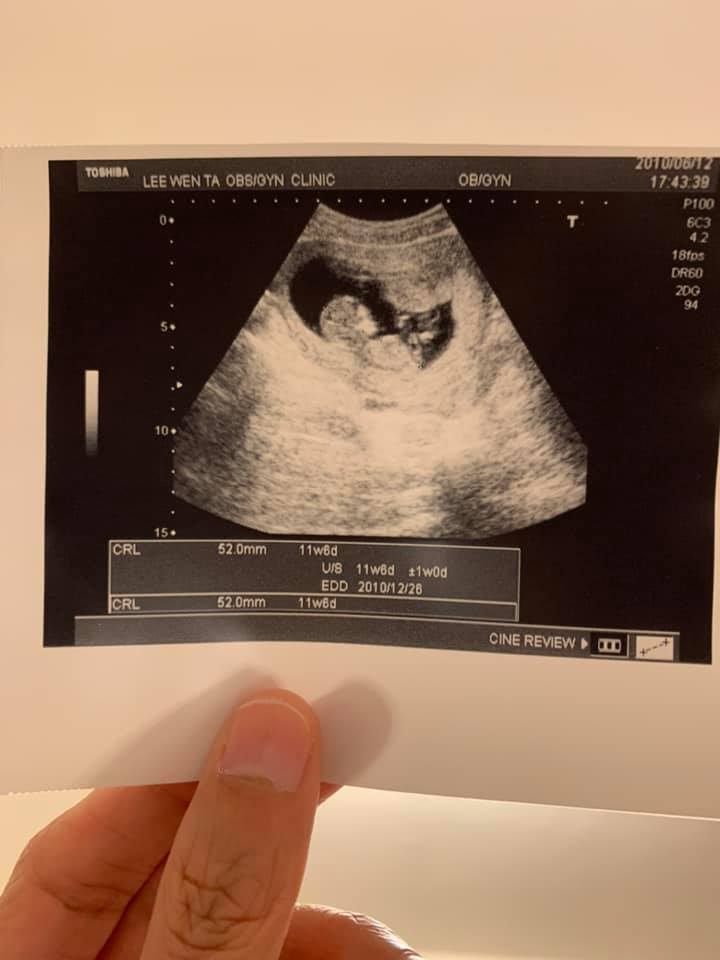

一個二十週的孕婦,跌躺在山坡上。